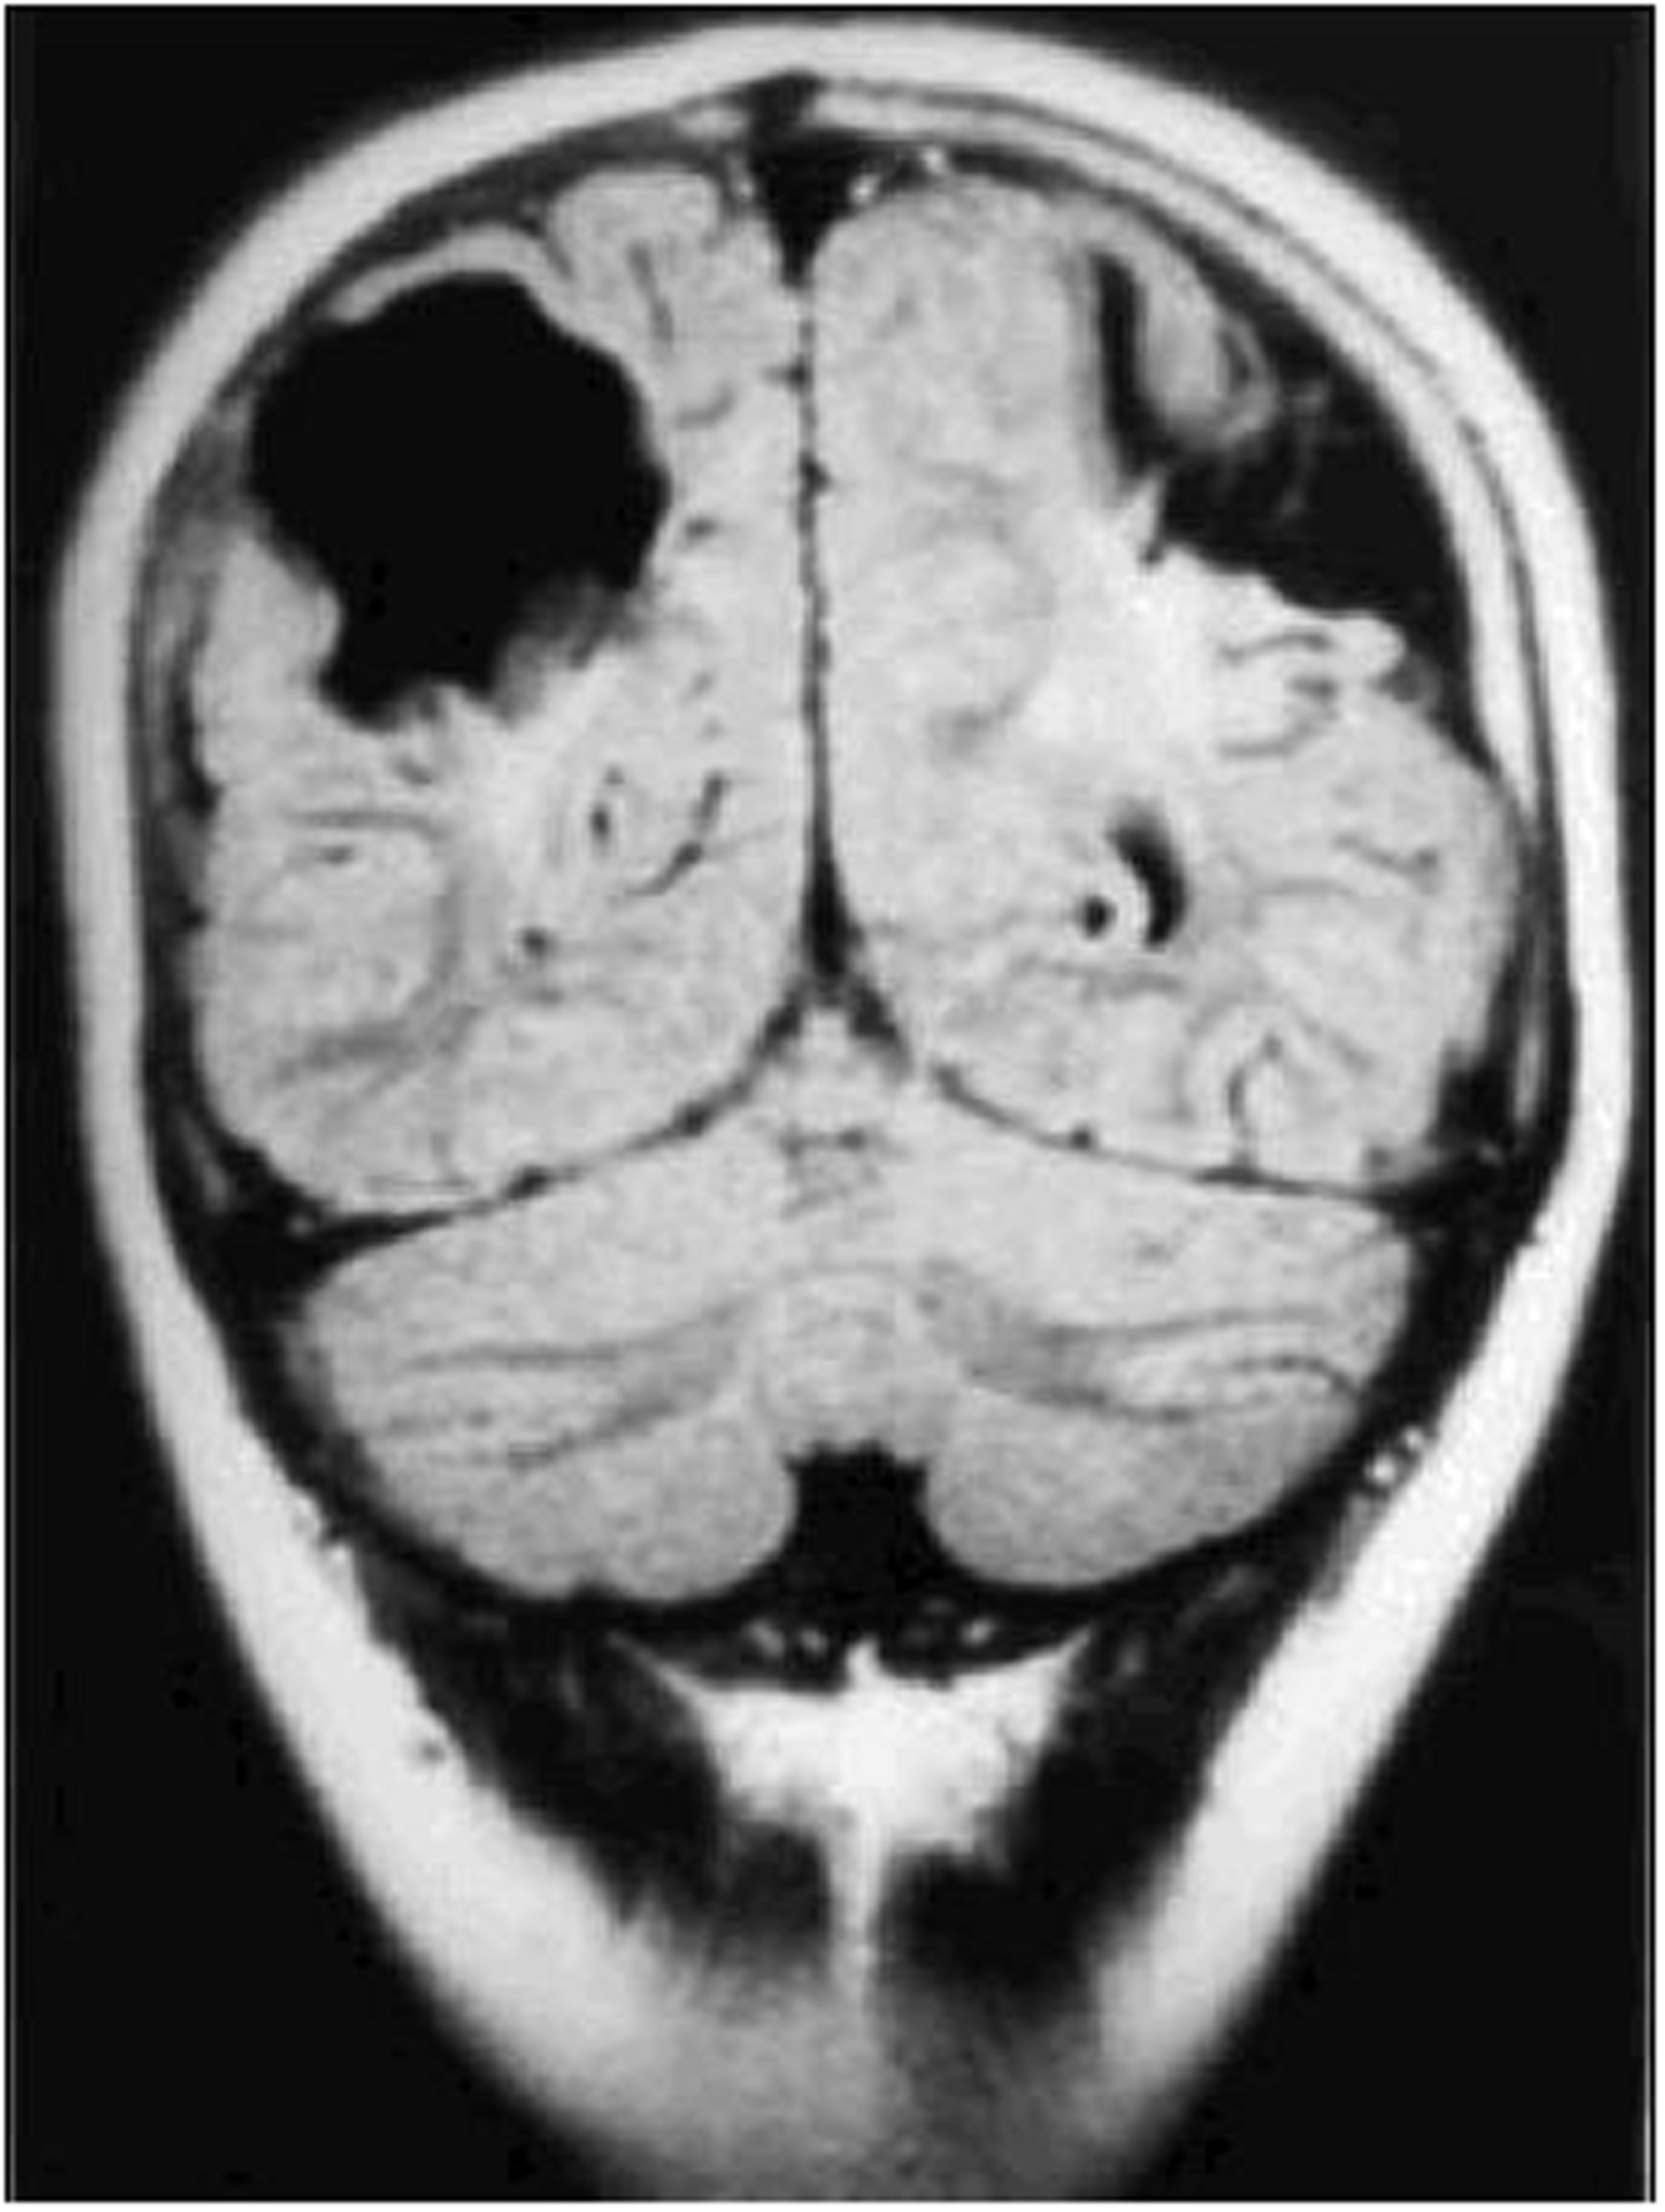

Damage to the parietal lobes results in defective three-dimensional mapping of the visual scene, with fewer of the surrounding entities in the scene being accessible for the frontal territory to accord attention to, culminating in simultanagnostic visual dysfunction (Barton, 2011). The impaired mapping also renders visual guidance of movement inaccurate (or optic ataxia), particularly when reaching to the side, as well as inaccuracy of, or inability to make visually guided saccades, despite evidence of an intact eye movement system (oculomotor apraxia). These features can occur singly or in combination. Severe variants of this condition comprise Balint syndrome (Rizzo and Vecera, 2002), while those that are less severe are commonly referred to as dorsal stream dysfunction (Macintyre-Beo et al., 2010). The superior optic radiations can also be affected, causing lower visual field impairment, which ranges between being complete, to solely rendering the feet invisible when walking. Impaired image resolution in the lower visual field (Jacobson et al., 2006) also impairs visual guidance of movement. Figure 3 (MRI scan of bilateral posterior parietal lobe scarring) shows bi-parietal damage due to perinatal hypoxic ischaemic encephalopathy.

FIGURE 3

Coronal CT scan of bilateral posterior parietal lobe scarring in a 10 years old boy with features of Balint syndrome. (Reproduced by the author GN Dutton, from Gillen and Dutton, 2003.)